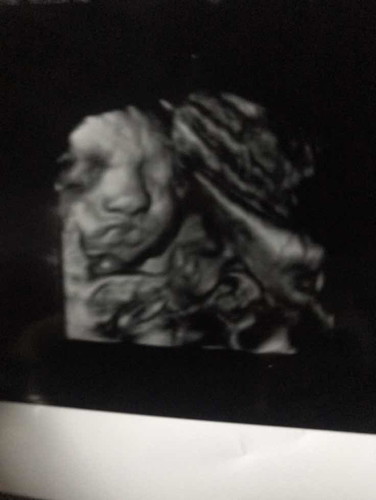

เเบบนี้ปากลูกเเหว่งไมคะ ใครรุ้ช่วยบอกหน่อยคะ. เเม่นี้จิตตก. เเต่ครั้งก่อนเคยถามหมอหมอบอกไม่เเหว่งเเต่ในภาพเเม่ดูไม่ออกคะ

อย่างงี้ไม่เรียกว่าปากแหว่งค่ะแม่เพราะในรูปริมฝีปากบนปกติส่วนปากล่างริมฝีปากของนัองหนาเท่านั้นเองค่ะ ถ้าปากแหว่าคุณแม่รองดูในกูเกิ้ลได้ค่ะไม่ใช่แบบนี้ไม่ต้องวิตกนะค่ะ

ตอนไปซาวก้ตกใจเหมือนค่ะถามหมอว่าแหว่งไหม แต่หมอบอกว่า อาจจะเป็นพวกสายต่างๆที่อยู่ในท้องแล้วอาจจะเป็นเงาจ้า

หมอบอกว่าไม่แหว่งก็ต้องเชื่อหมอค่ะอย่ากังวลเลยค่ะแม่ดูแล้วเหมือนน้องทำปากจู๋😘

ไม่แหว่งคะ บ้านนี้กะแบบนี้คะ หมอบอก น้องดูดปากอยุ่คะ เลยได้ภาพออกมาแบบนี้😂

ถ้าหมอบอกปกติก้อน่าปกตินะคะแม่ระหว่างปากถึงจมูกเนื้อเต็มปกตินะคะ